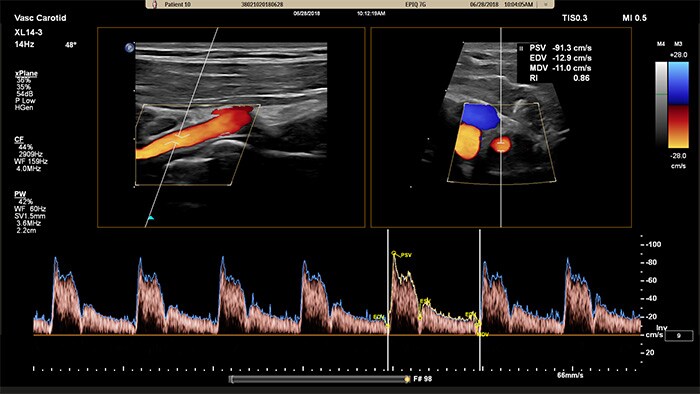

Doppler xPlane

El XL14-3 xMatrix también ofrece funciones de Doppler xPlane. El Doppler pulsado xPlane permite una colocación precisa del volumen de muestra mediante Doppler a través de imágenes de referencia longitudinales y transversales. La principal ventaja: el Doppler xPlane reduce los errores de colocación del volumen de muestra y ofrece una mayor reproducibilidad y coherencia a la hora de tomar muestras de estenosis pronunciadas.